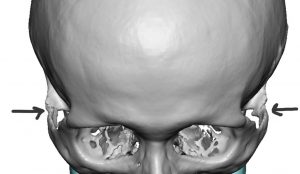

While the different styles and sizes of standard cheek implants can fulfill many cheek augmentation needs, the use of preformed implants can not satisfy every patient’s aesthetic needs. Custom cheek implants, designed from the 3D CT scan of the patient, has a useful role to play in several specify needs such as a specific aesthetic effect (e.g., high cheekbone bone look or extended cheek-arch styles), when cheekbone asymmetries exist (e.g., facial asymmetry) and for revision of previously unsatisfactory cheek augmentation results using preformed implants.